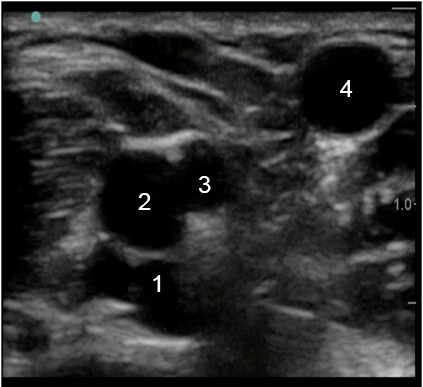

Vessel Assessment (upper arm) Image

Brachial Vein

Brachial Artery

Basilic Vein